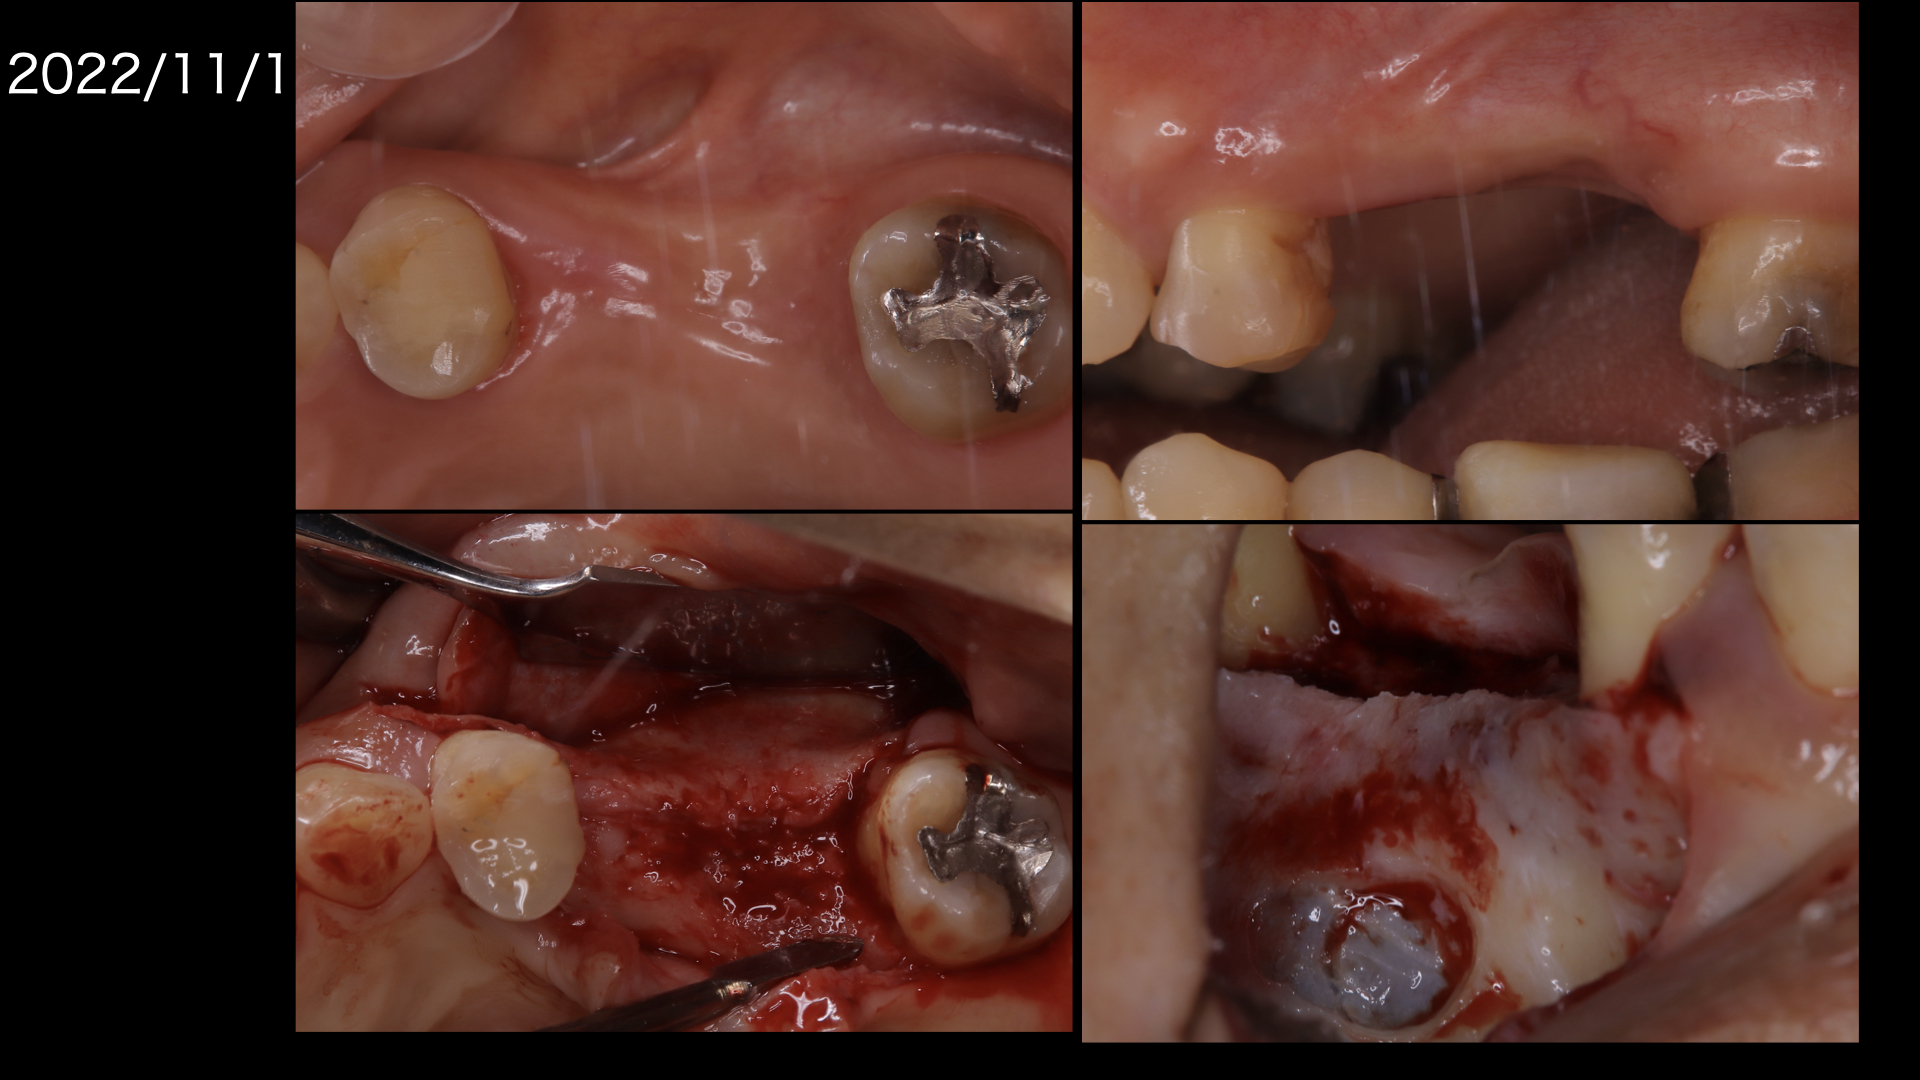

左上の歯が痛い。ということが主訴で紹介で来られました。左下や真ん中の写真をみてください。

前歯がしっかり噛んでいません。

左上は支えている骨が大きく吸収しています。

まずは奥から2番目の歯も保存を希望されましたが、治りが悪かったので一度抜歯して歯石を取り、戻してみて保存を試みました。

その間矯正治療をおこないました。

残念ながら、奥歯は腫れが引かず抜歯になってしまいました。